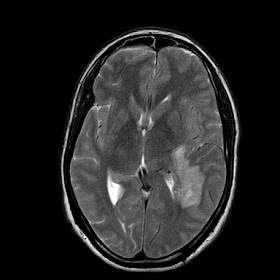

A 35 years old man MRI